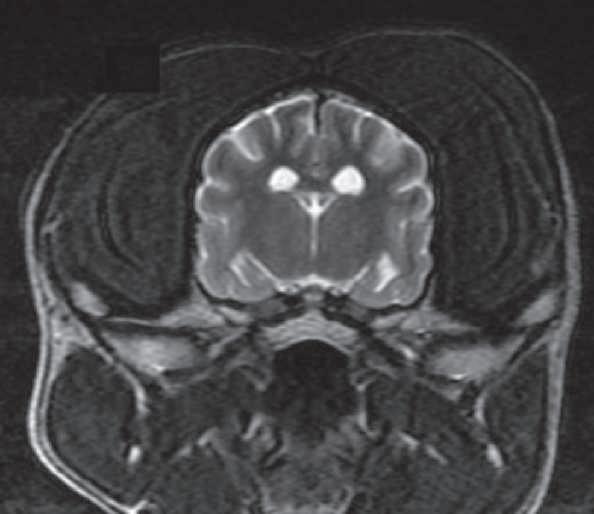

Tracto corticoespinal en vista coronal. (p. ??).

Uso del tensor de difusión como una herramienta de diagnóstico en las enfermedades del sistema nervioso central en perros. Reporte de un caso en un husky siberiano con alteraciones del comportamiento.

Use of the diffusion tensor as a diagnostic tool in diseases of the central nervous system in dogs. Report of a case in a Siberian husky with behavioral alterations. .